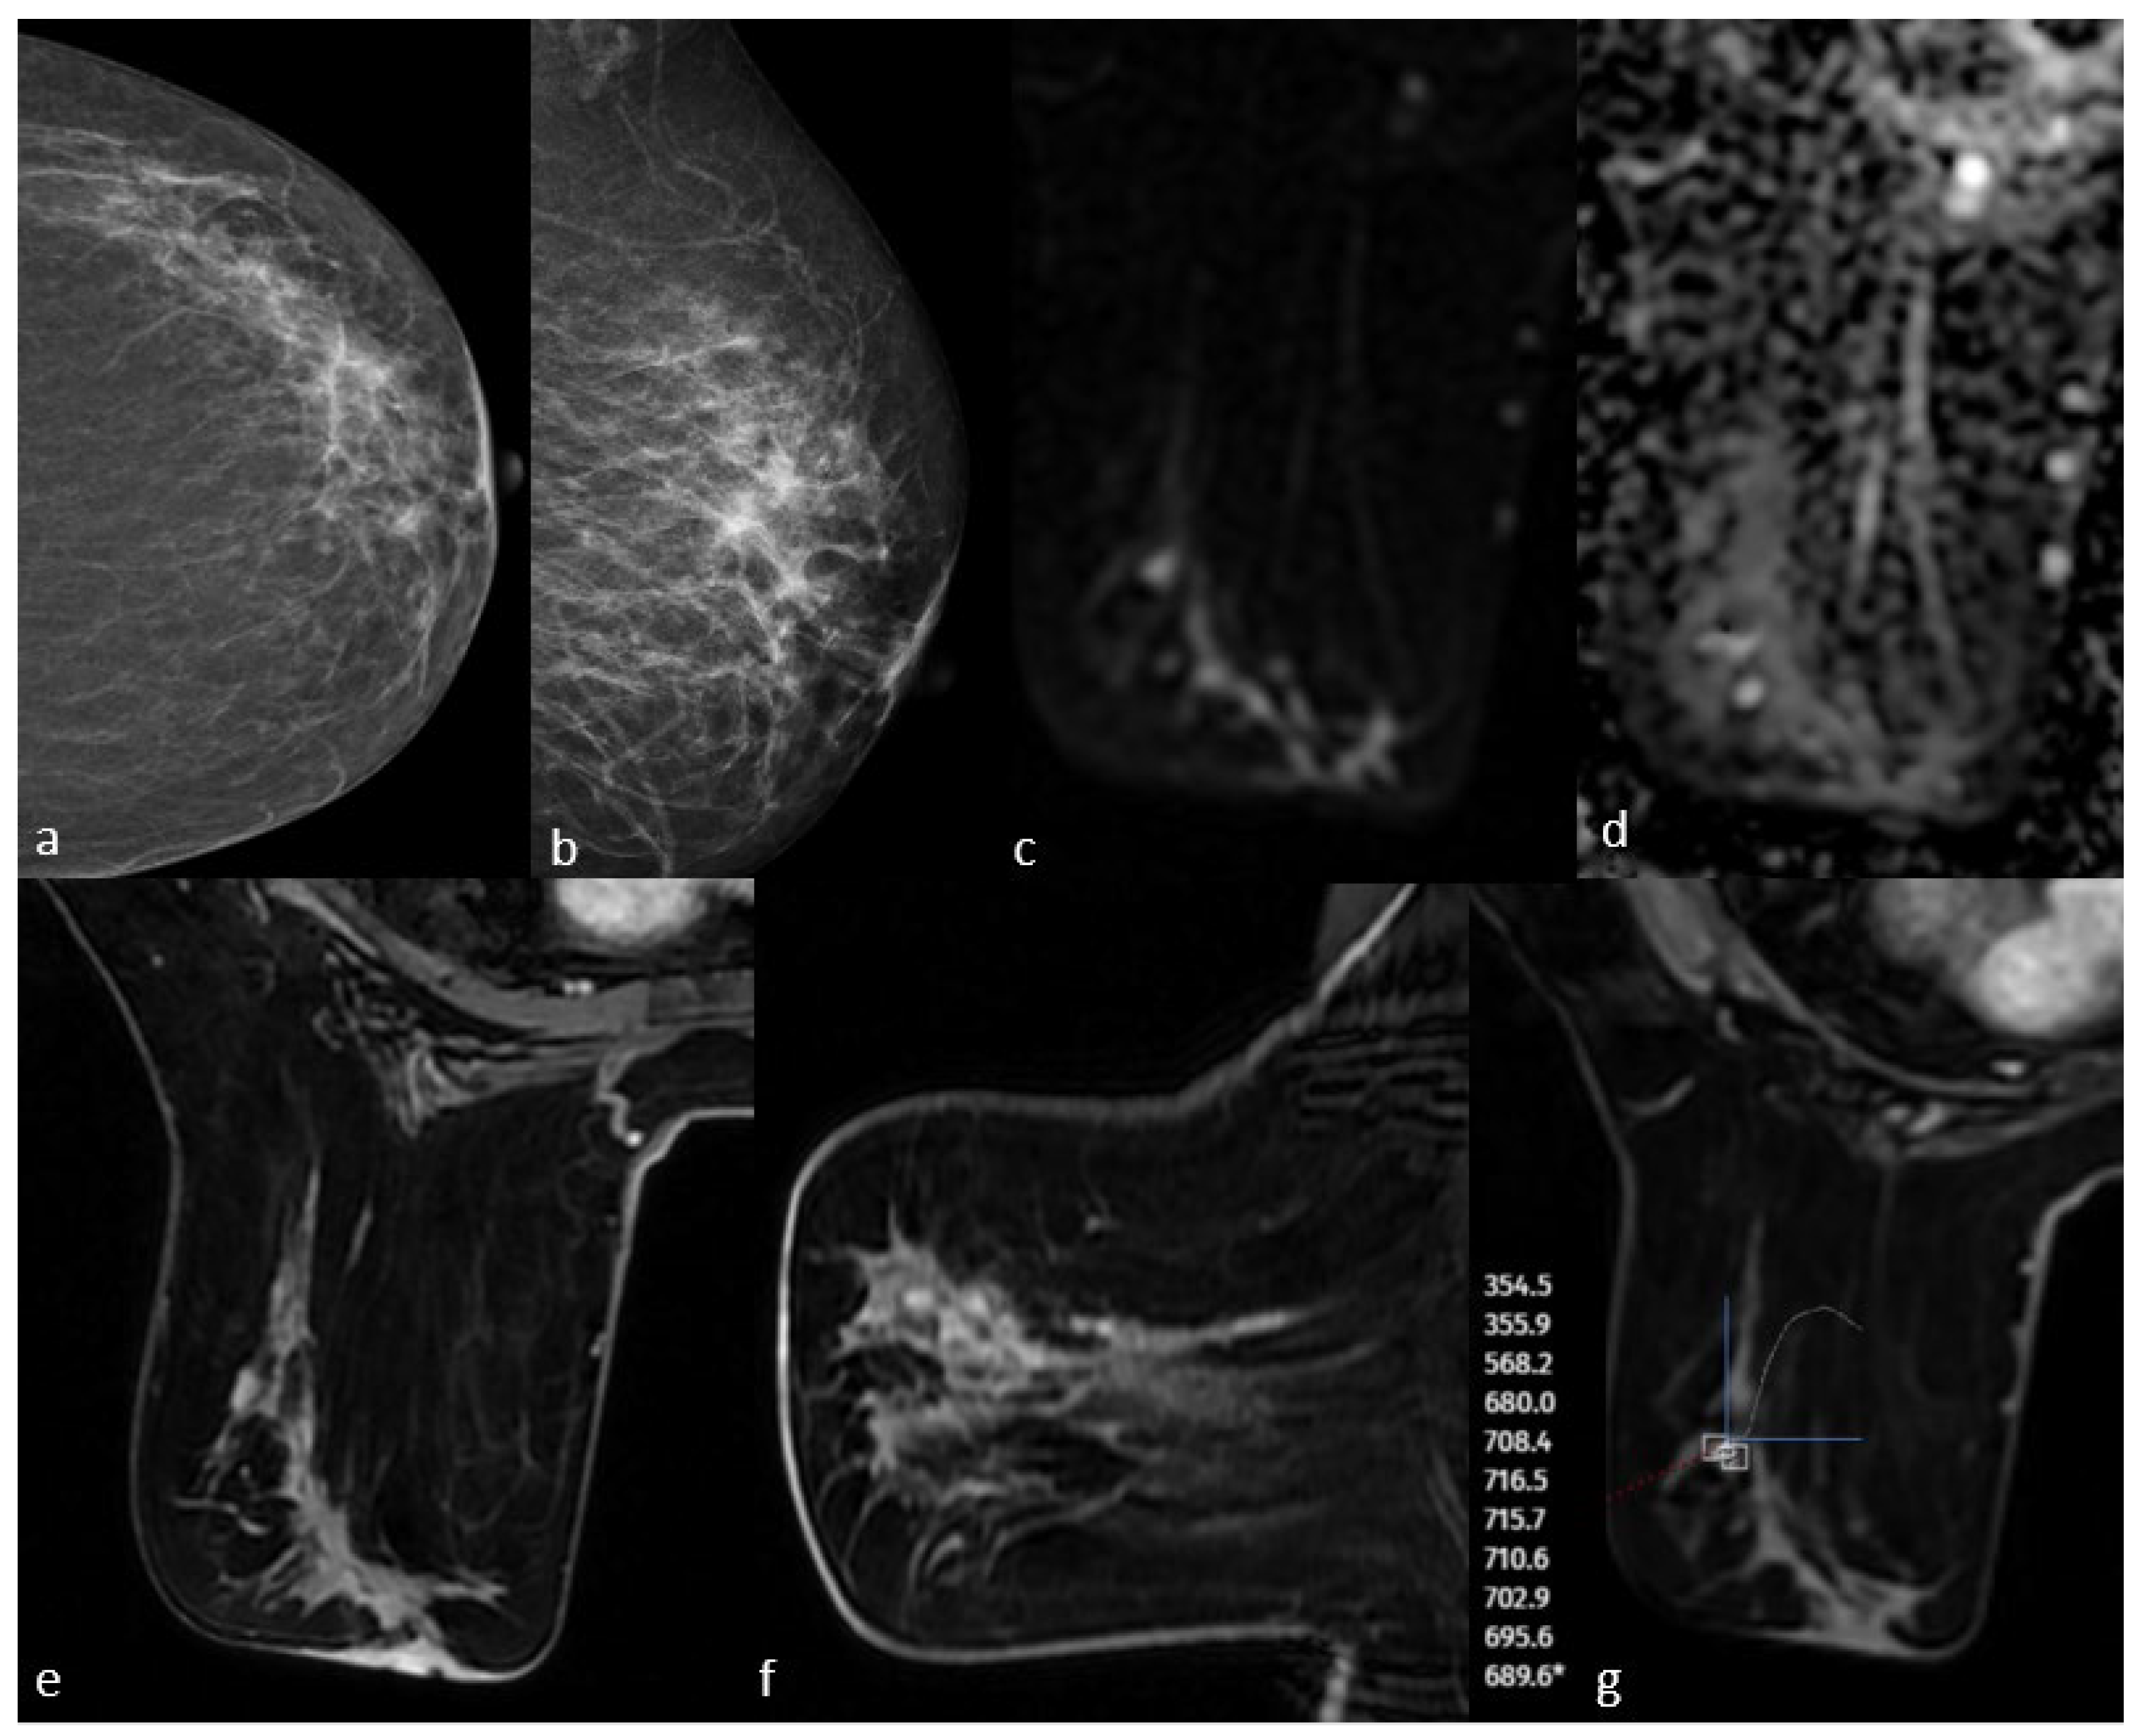

3.1. Mammographic Findings

3.2. Magnetic Resonance Imaging Findings